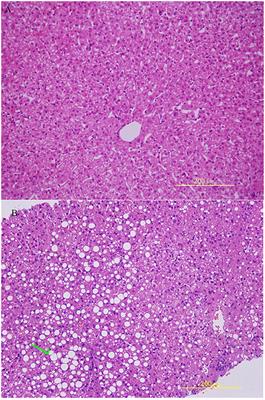

Histopathological Features and Composition of Gut Microbiota in Rhesus Monkey of Alcoholic Liver Disease

in Gastrointestinal Sciences